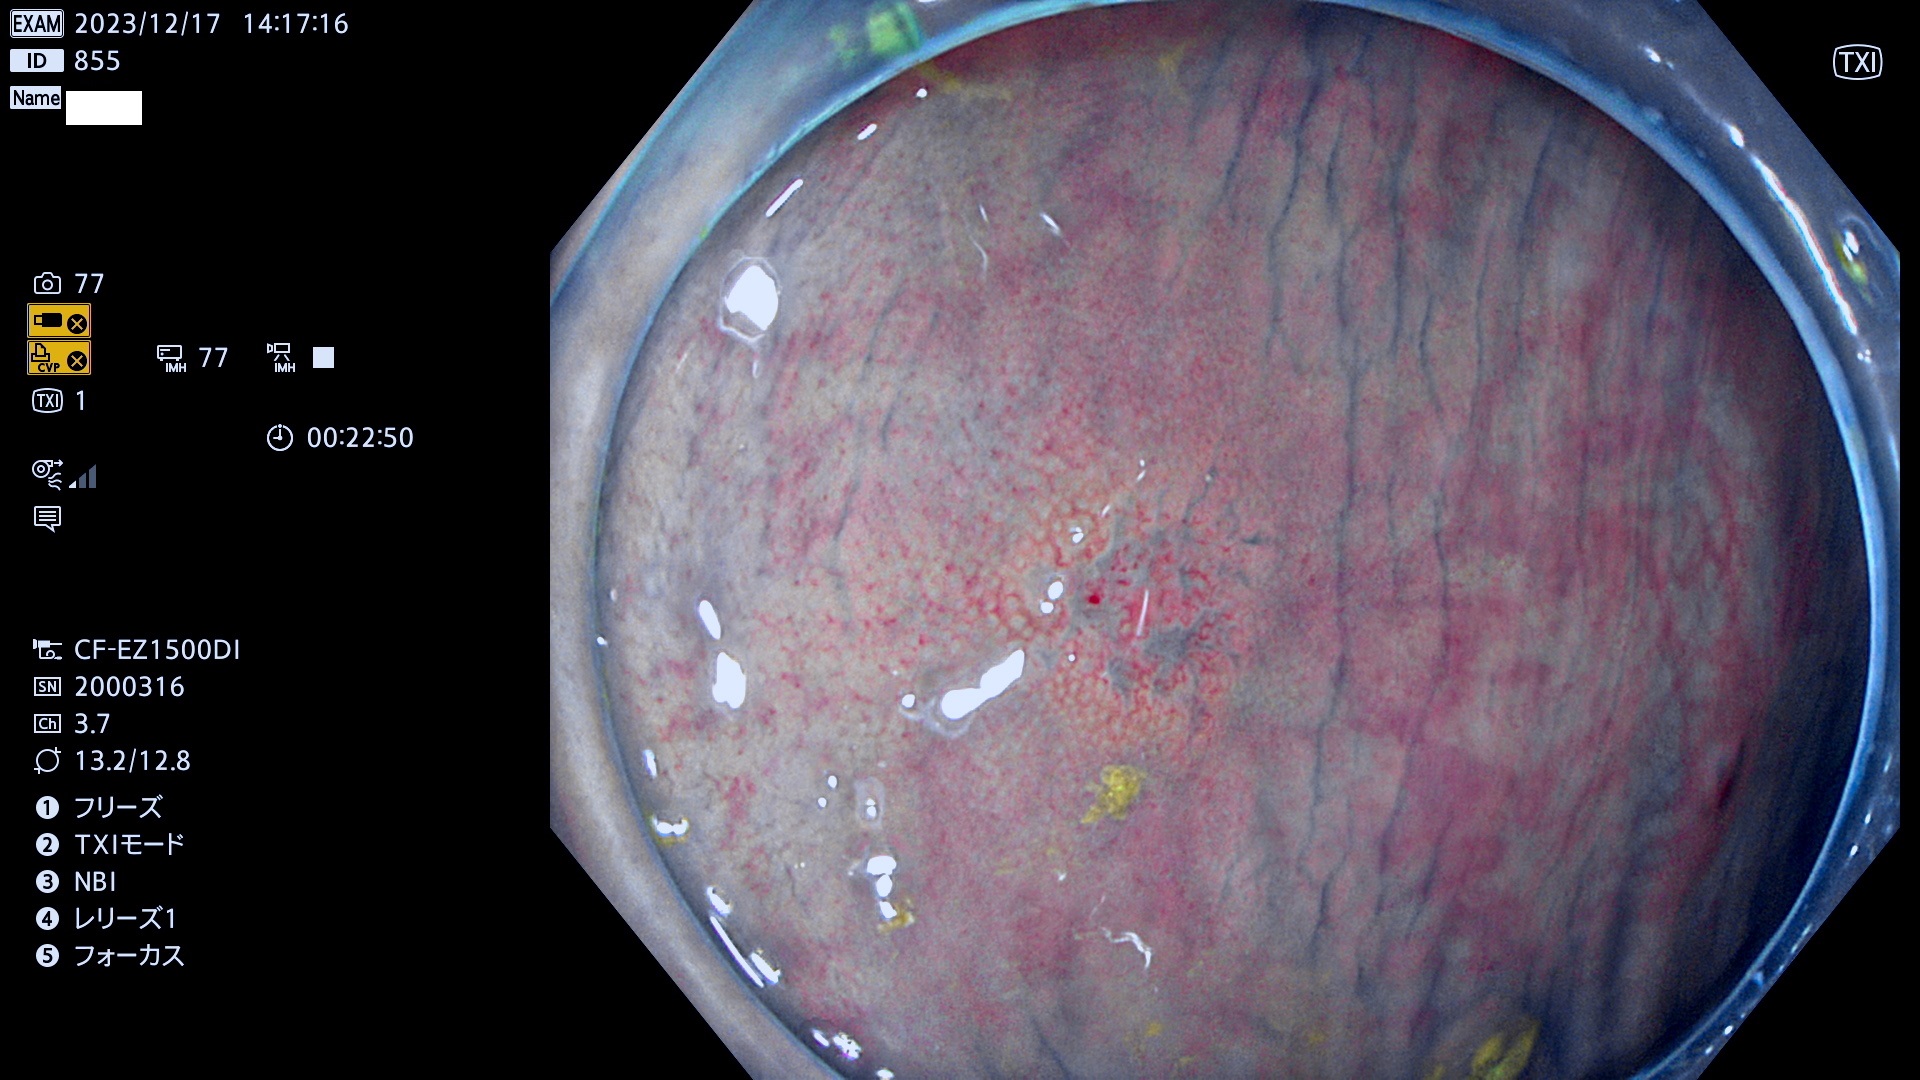

表面型腺腫(Flat Adenoma)の中で、完全に平坦な物をUb、陥凹している物をUcと呼びます。平坦隆起型(Ua)よりも、発見が難しく危険な病変です。このタイプは「内視鏡後・大腸癌の重要犯人」であり、この発見率は「腺腫発見率」よりも、重要な意味があります。

毎週の検査(木・金・土・日)に発見されたUb、Uc型・腺腫を、その週の日曜の夜にUPし1週間、提示します。

抽出の対象期間 2023年12月14日(木)〜12月18(日)の5日間(60件の検査)7件

当院で発見された炎症(ビラン)と紛らわしい腺腫